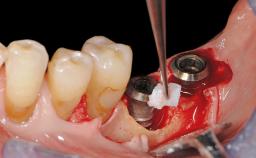

Treatment of Peri-Implant Mucositis at a Zirconia Implant

Recent clinical studies, most with short-to-medium term observation periods, have reported on the favorable clinical performance of zirconia implants in terms of survival rates, clinical, and radiographic outcomes (Roehling and coworkers 2016; Roehling and coworkers 2017; Rodriguez and coworkers 2018; Lorenz and coworkers 2019). Nonetheless, a rather high incidence of peri-implant disease at zirconia implants (39% of implants) was noted throughout a two-year period, highlighting the need for treatment protocols of peri-implant diseases at zirconia implants (Becker and coworkers 2017).